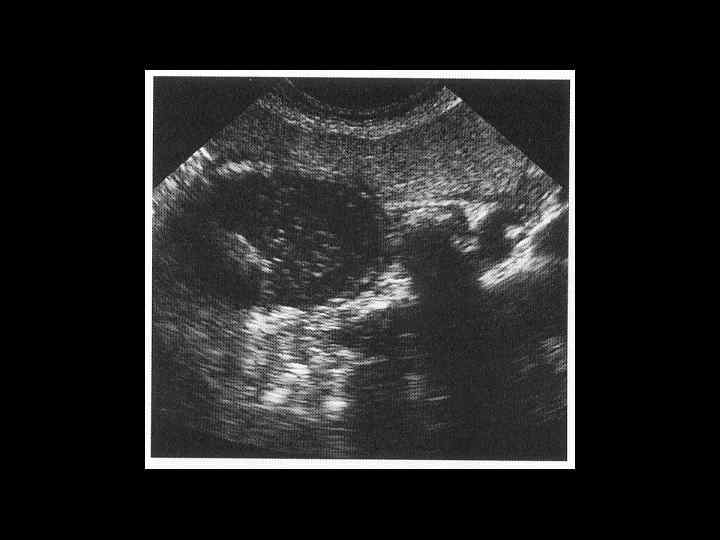

АКТУАЛЬНЫЕ ВОПРОСЫ РЕНТГЕНОЛОГИИ ЛУЧЕВАЯ ДИАГНОСТИКА ЗАБОЛЕВАНИЙ ЖЕЛЧЕВЫДЕЛИТЕЛЬНОЙ СИСТЕМЫ Желчекаменная болезнь УЗ семиотика